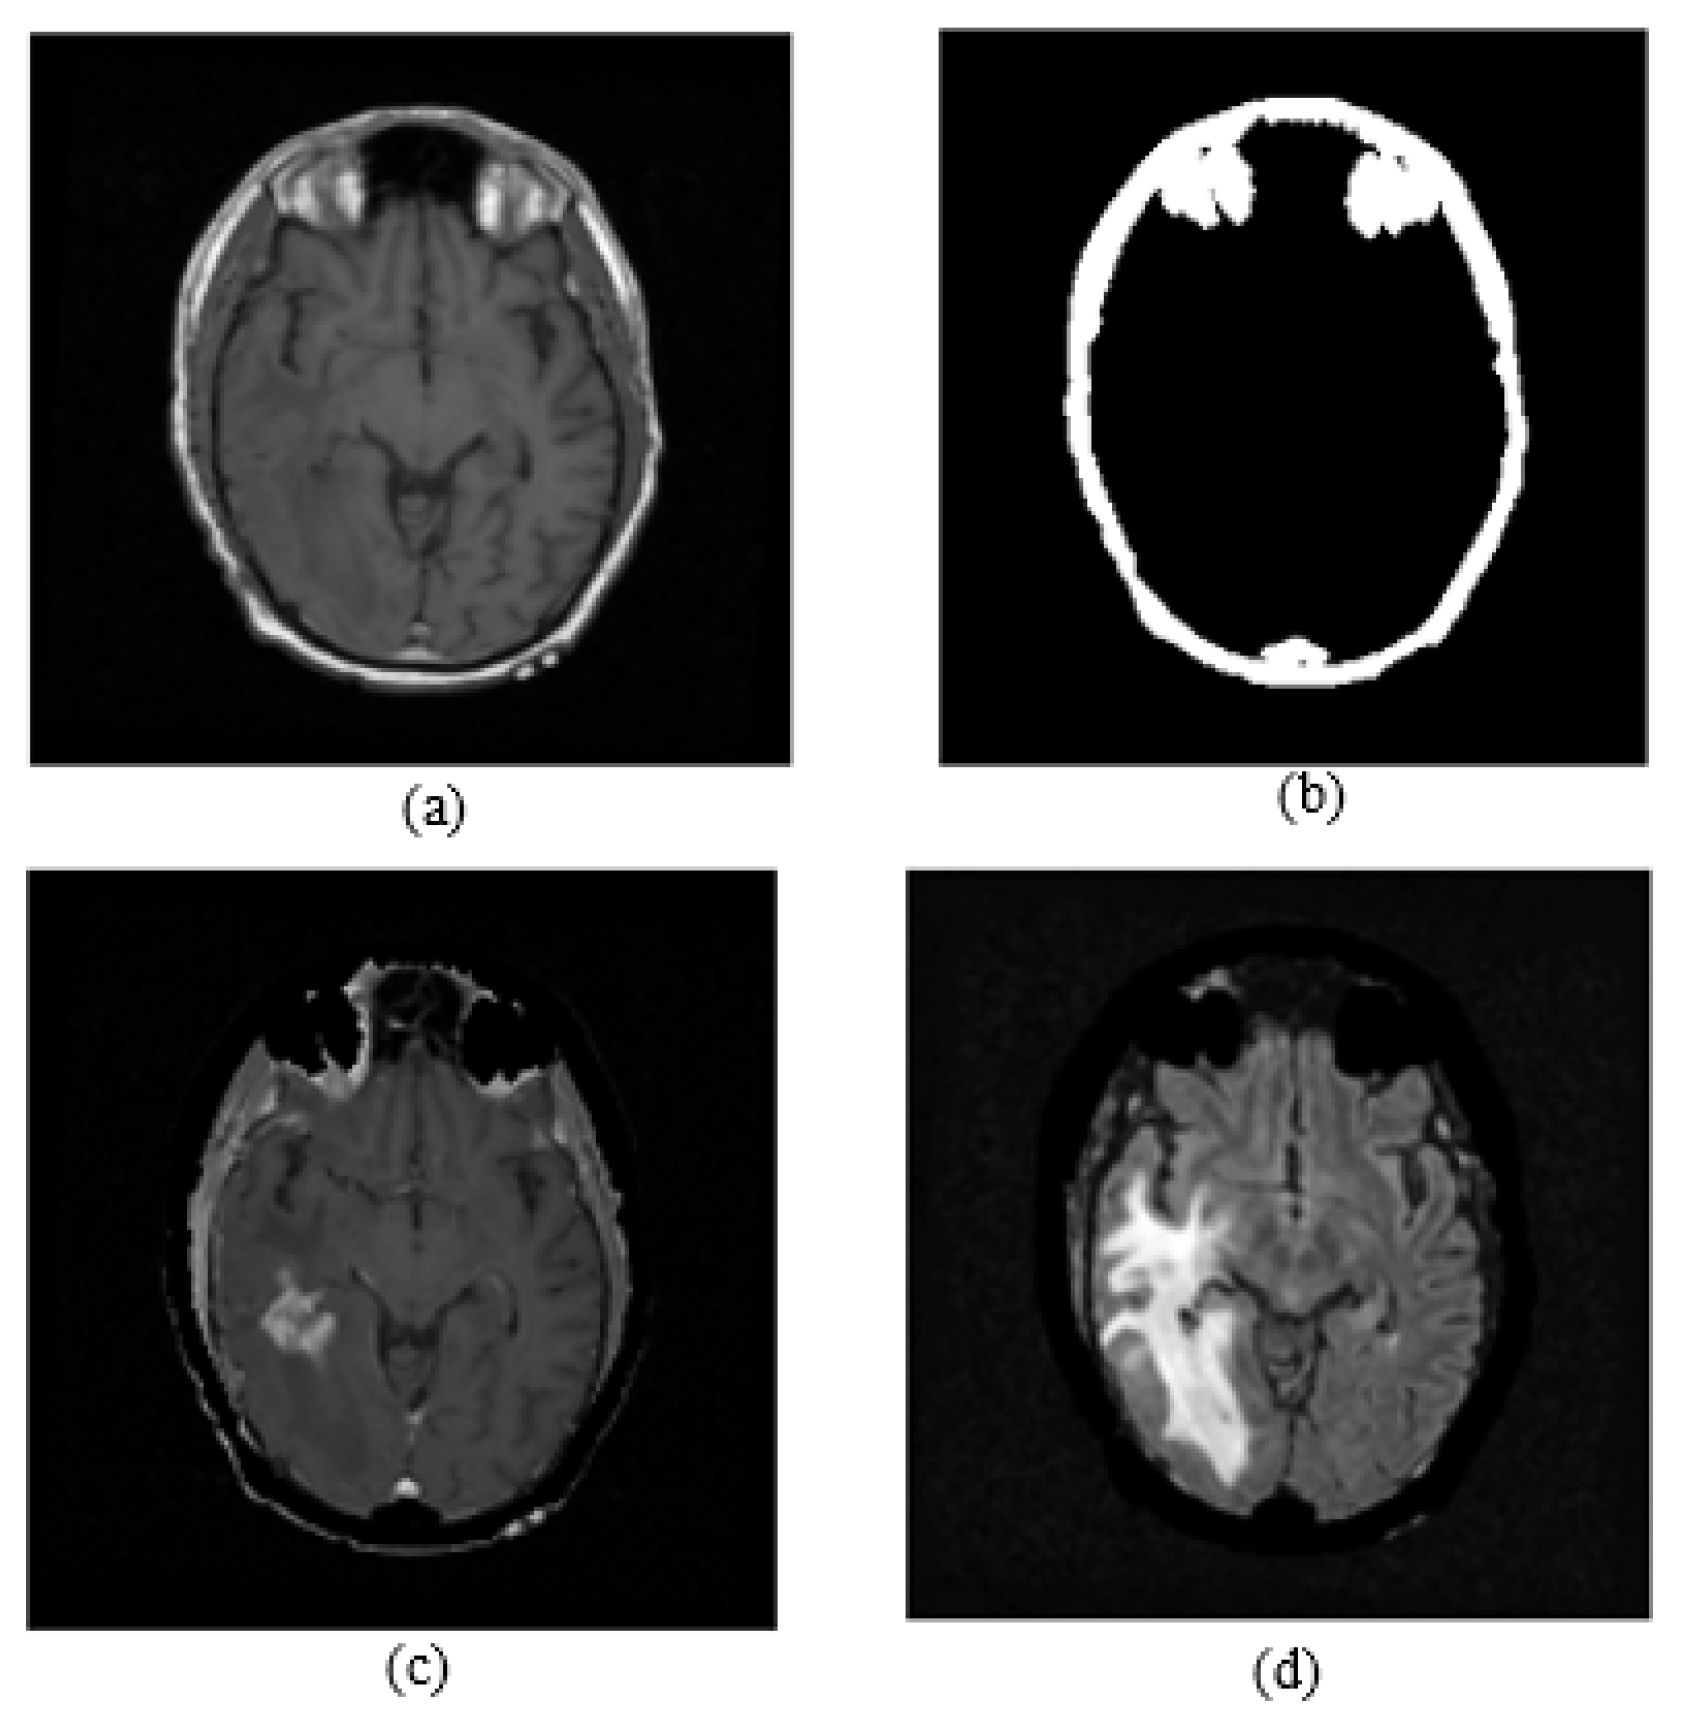

Non-brain regions such as the skull, orbital fat, and sclera in the brain MR images led to confusion in the tumor detection process, because these irrelevant parts have the same intensity level as tumor regions. In the T1C images, the skull, eyes, and tumor regions have high intensity level, while in the T1 images, only the skull and eye regions have high intensity, so the T1 images were used as a skull-stripping mask to remove irrelevant regions. A skull stripping block diagram is shown in Figure 4. To obtain the skull-stripping mask, an adaptive thresholding operation was applied to the T1-weighted images by using the threshold values assigned automatically in the histogram analysis part of the algorithm. A T1 image and the obtained skull stripping mask are shown in Figure 4. After obtaining the skull-stripping mask, the skull and eye regions of the FLAIR images were removed by a masking operation. Figure 5 shows a T1 image, a skull stripping mask, a skull-stripped T1C image, and a skull-stripped FLAIR image are given.

Figure 4.

Figure 5.

(a) T1 image; (b) skull stripping mask; (c) masked T1C image; (d) masked FLAIR image.